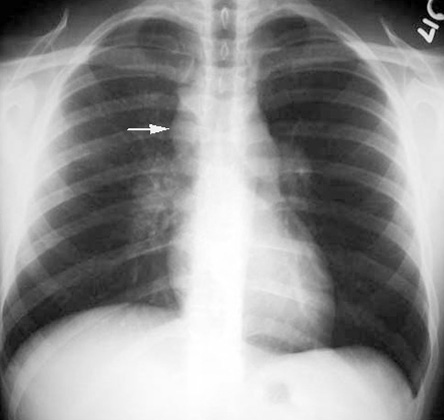

Sarcoidosis

paratracheal nodes